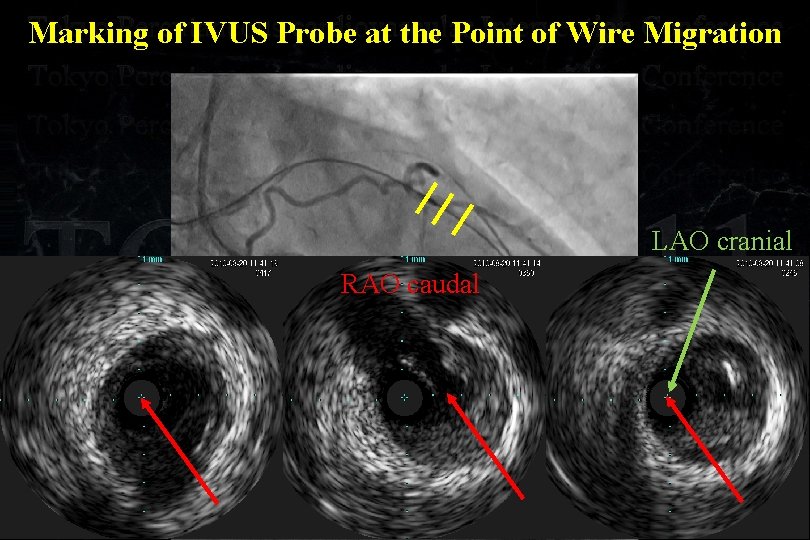

Marking of IVUS Probe at the Point of Wire Migration

Marking of IVUS Probe at the Point of Wire Migration

Marking of IVUS Probe at the Point of Wire Migration LAO cranial RAO caudal